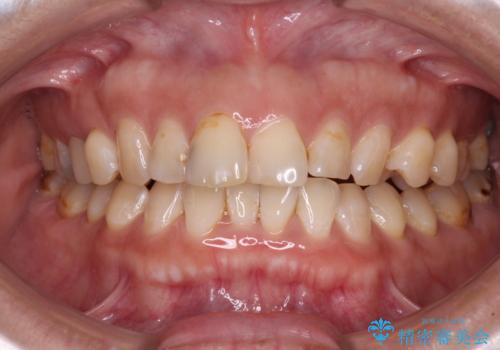

[ 前歯開咬 ] 前歯が噛んでいない マウスピース矯正治療

担当医 大元洋佑